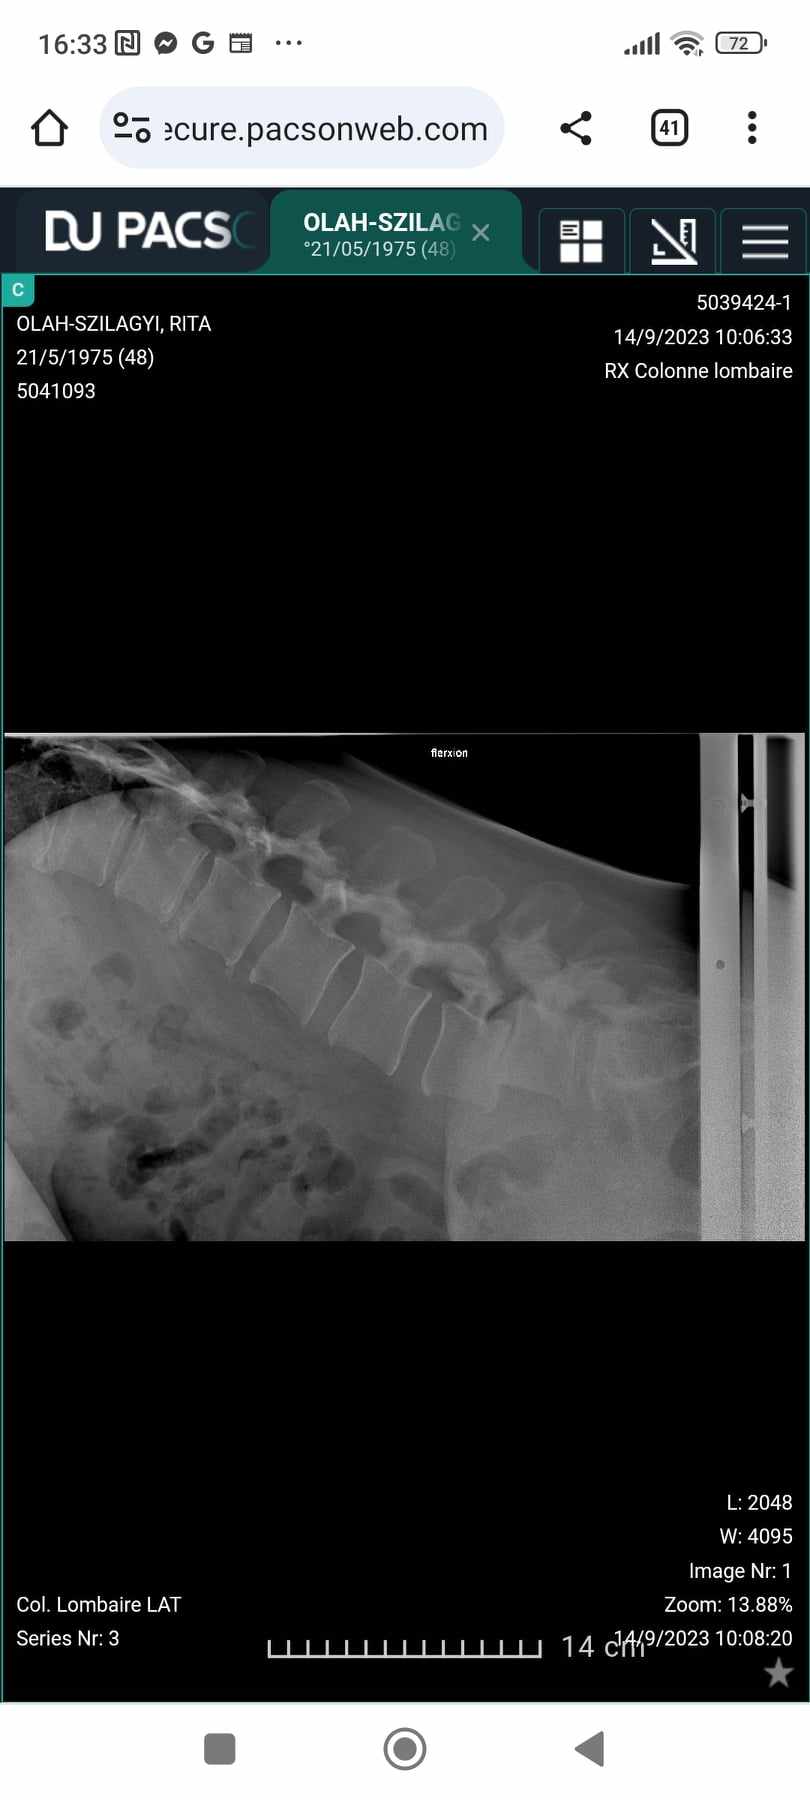

Az én esetemben sajnos gyógyulásról nem lehet szó, mert az elcsúszott, elmeszesedett, artritiszes (állandó gyulladásban lévő) csigolyáimat csak műtéti úton lehetne a helyükre visszatenni. Ezt egyelőre nem akarják az orvosok megtenni az ágyéki (L4-L5) csigolyáimnál, arra hivatkozva, hogy még túl fiatal vagyok. Tehát a kiné csak a fájdalom enyhítésében tudna segíteni, ha...

Legelőször akkor találkoztam kinével, amikor 2014-ben diagnosztizálták a betegségemet. Csigolyacsúszások a gerincemen 1 a nyaki részen (C5-C6) és egy az ágyéki részen (L4-L5). Akkor a neurológus úgy engedett haza a konzultációról, hogy döntsem el melyiket akarom először műttetni a nyakamat vagy az ágyéki részt, addig felírt 18 alkalom kinét.

Az én L4-es csigolyám már 8,5 mm-re van elcsúszva a hasfal felé, ül az L5-ös csigolyán. Nem gondolom, hogy bármilyen jól irányzott mozdulattal ezt vissza lehetne helyezni a helyére.

A megbeszélt találkozóra 40 perc késéssel megérkezett egy 23 éves lányka kiné. Elvette az orvosi beutalómat, biztosan nem olvasta el, mert annyi idő alatt nem lehet, és kezdtük a kezelést. Ő is egy székre ültetett, hozta a testápolóját és kezdett masszírozni. Felment az agyvizem. Hogy lehet széken ülve, ami az én hátamnak a legrosszabb pozíció, masszírozni? Amikor a lányom masszíroz fekve az ágyon szakértelem nélkül, az esküszöm hasznosabb. Ezt nevezik gyógymasszázsnak? Majd lefektetett a szőnyegre a hátamra és olyan feladatokat kezdett csináltatni, ami lehetetlennek tűnt. Nem tudok homorítani, még a röntgenen is probléma volt mikor kérték, hogy hajoljak hátrafelé a felvétel kedvéért. Közöltem vele, hogy ilyen jellegű gyakorlatokat már 8 éve nem csinálhatok. Azt kérdezte: - Miért? Mondtam azért, mert ezek tovább csúsztatják a csigolyáimat a rossz irányba. Látszott rajta, hogy nem érti az aggályaimat, én pedig meggyőződtem róla, hogy fogalma sincs arról mi a betegségem. Letöltöttem az Internetről a saját orvosi oldalamról a gerincemről készült MRI felvételeket és a következő alkalommal megmutattam neki. Elképedve nézte, mennyire deformált a gerincem. Leesett neki, miért mondtam az előző feladataira, hogy nem hasznosak.